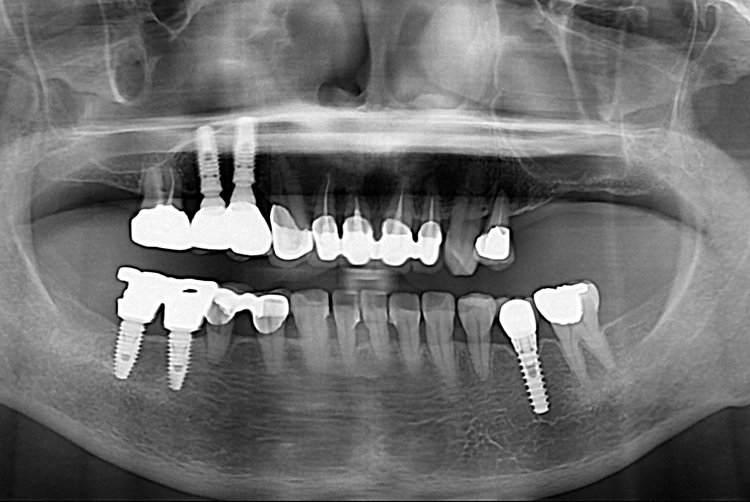

[임플란트] 어금니 임플란트

치료후 : 2019-02-13

세종치과는 많은 환자와 다양한 케이스를 바탕으로

항상 편안한 임플란트 수술을 제공하고자 노력하고,

오래동안 튼튼히 쓸 수 있는 임플란트 수술을 가장 큰 목표로 삼고 있습니다.